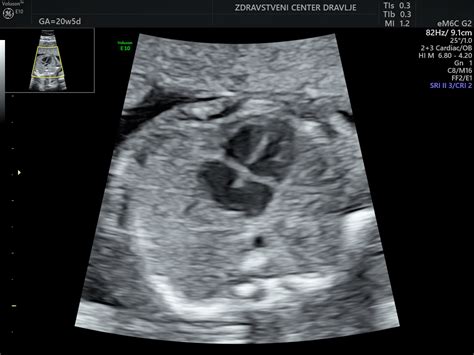

Čeprav dvojni hormonski test sam po sebi zagotavlja določeno mero informacij, so rezultati bistveno bolj zanesljivi, kadar se kombinirajo z meritvijo nuhalne svetline. Nuhalna svetlina je debelina žepa tekočine pod kožo na zatilju ploda, ki se meri z ultrazvokom. Ta meritev se običajno opravi med 11. in 14. tednom nosečnosti. Povečana nuhalna svetlina je lahko znak povečanega tveganja za kromosomske nepravilnosti, kot so Downov sindrom, Edwardsov sindrom in Patau sindrom, pa tudi za druge razvojne nepravilnosti ali srčne napake.